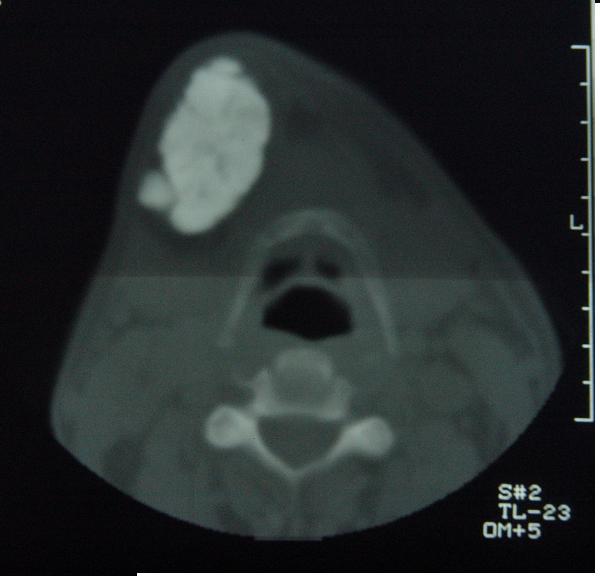

标题: CT12465:下颌骨肿瘤,请会诊 [打印本页]

标题: CT12465:下颌骨肿瘤,请会诊

发现下颌骨肿瘤近30年.逐渐增大.

位置及病程较长考虑:造粙细胞瘤

造釉细胞瘤,没有特征性;半月切迹?骨间隔?多房性骨密度减低区,大小不等。鉴别;动脉瘤样骨囊肿,骨软骨瘤。本人,更倾向于---骨软骨瘤。

考虑右侧下颌骨骨化性纤维瘤。